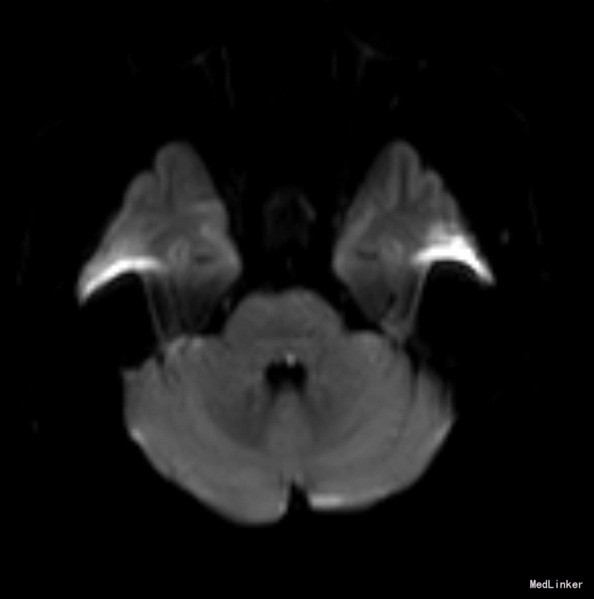

老年女性,急性起病。查体可见左眼内收受限,双眼右视时有水平眼震。影像学提示左侧桥脑背侧梗塞。与临床相符。考虑前核间性眼肌麻痹。 附上另一例前核间性眼肌麻痹头MRI,如图: